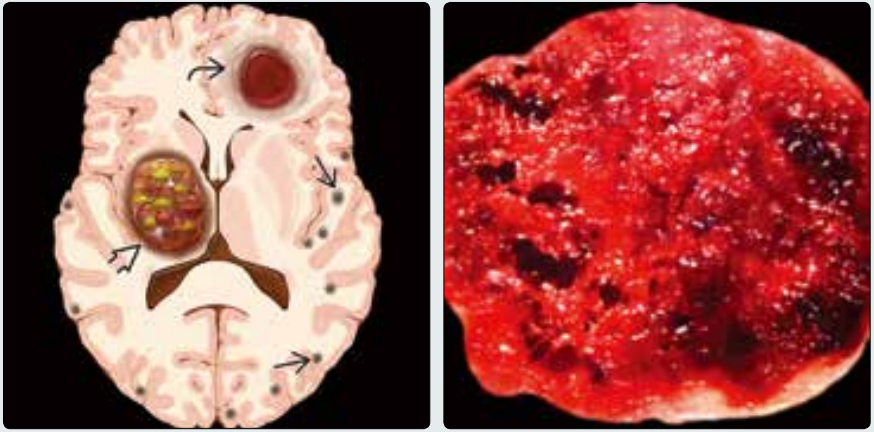

(左图)横断位示意图显示不同时期的海绵状血管畸形。右侧基底节见混杂信号(“爆米花球”征),为Zabramski 2型⇒,左额叶见亚急性出血伴水肿,为Zabramski 1型↪。多发性陈旧微出血(Zabramski 4型)表现为多灶性的黑点→。(右图)海绵状血管畸形大体病理切面,可见多房内不同时期的出血